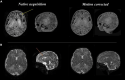

The Developing Human Connectome Project has created a large open science resource which provides researchers with data for investigating typical and atypical brain development across the perinatal period. It has collected 1228 multimodal magnetic resonance imaging (MRI) brain datasets from 1173 fetal and/or neonatal participants, together with collateral demographic, clinical, family, neurocognitive and genomic data from 1173 participants, together with collateral demographic, clinical, family, neurocognitive and genomic data. All subjects were studied in utero and/or soon after birth on a single MRI scanner using specially developed scanning sequences which included novel motion-tolerant imaging methods. Imaging data are complemented by rich demographic, clinical, neurodevelopmental, and genomic information. The project is now releasing a large set of neonatal data; fetal data will be described and released separately. This release includes scans from 783 infants of whom: 583 were healthy infants born at term; as well as preterm infants; and infants at high risk of atypical neurocognitive development. Many infants were imaged more than once to provide longitudinal data, and the total number of datasets being released is 887. We now describe the dHCP image acquisition and processing protocols, summarize the available imaging and collateral data, and provide information on how the data can be accessed.